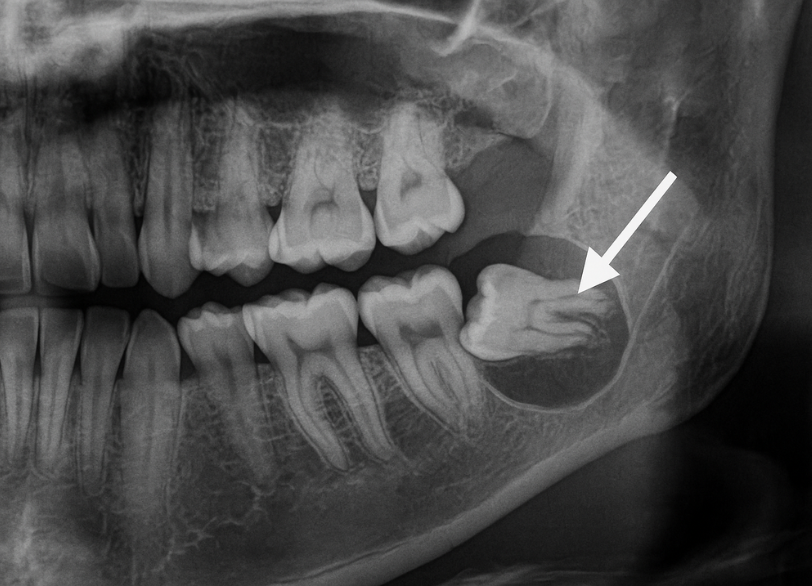

まず、レントゲン撮影を行い親知らずの生え方、歯の根の形、骨の中に埋まっている深さ、神経や血管との位置関係などを正確に把握します。

親知らずの根が下顎の中を通る太い神経に近接している場合や、極めて深い位置に埋まっている場合など処置の難易度が非常に高いケースも存在します。

当院では安全を第一に考え、CT撮影による精密な診断が別途必要と判断される症例や全身的な配慮が求められる患者様につきましては、連携する地域の基幹病院や大学病院の口腔外科を速やかにご紹介する体制を整えています。